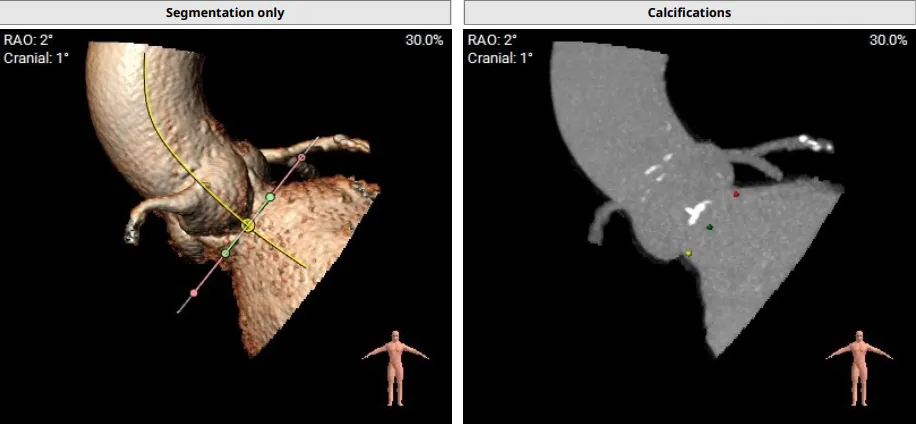

患者为主动脉 Type I 型二叶瓣,左无瓣叶交界处钙化融合,瓣叶稍增厚;存在三个瓣窦,分布较均匀;主动脉瓣环周长折算直径27.0mm;双侧冠脉开口高度可LCA:12.9mm;RCA:15.1mm;双侧冠脉开口高度可,右侧冠脉开口处扩张,双侧冠脉点状钙化;最佳投射角度:右窦中心位:CRA:1°/RAO:2°(其他参考角度如下图);左室主动脉夹角为159°; 模拟切口位置:第6-7肋间;模拟输送器角度为149°。

患者为主动脉瓣三叶瓣,瓣叶增厚,瓣叶未见明显钙化,存在三个瓣窦,窦部增大,分布较均匀;主动脉瓣环周长折算直径29.4mm;双侧冠脉开口高度可LCA:10.9mm,RCA:17.2mm;双侧冠脉未见明显钙化;最佳投射角度:右窦中心体位:CRA:16°/LAO:13°(其它参考角度如下图); 模拟切口位置:第6-7肋间;模拟输送器角度为143°;室间隔基底部稍增厚;升主动脉人工血管置换术后。